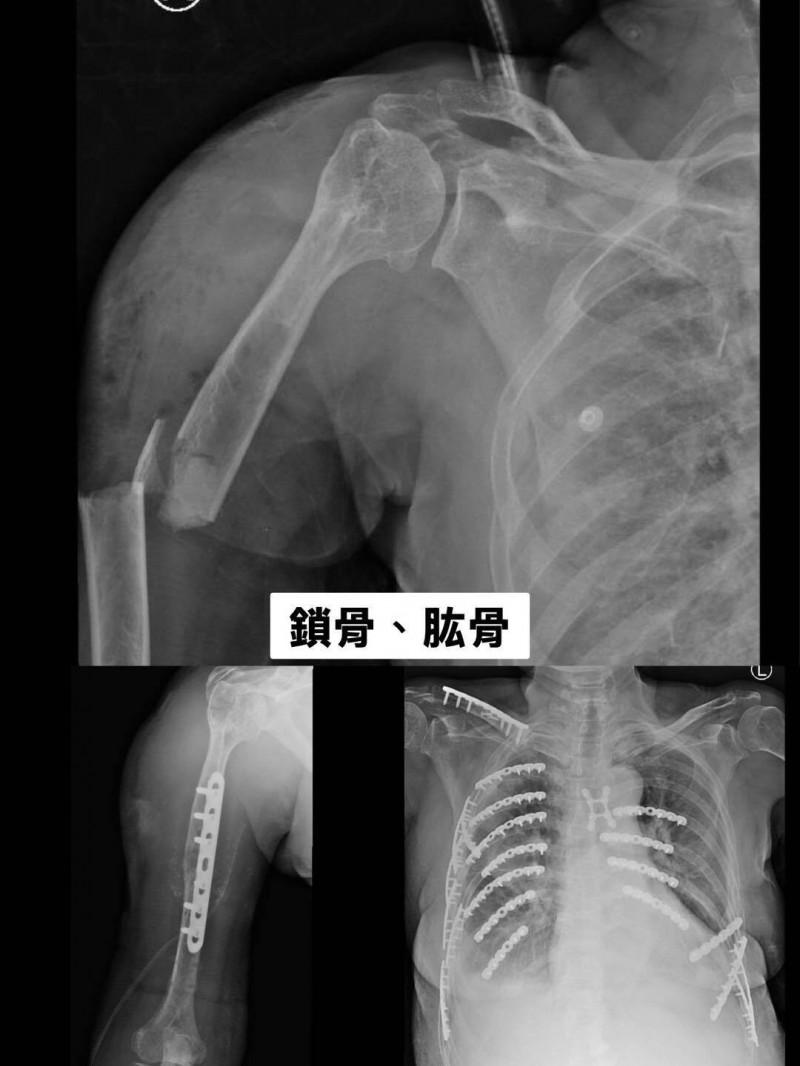

黃婦到院時傷勢極為嚴重,檢查發現其右上臂開放性骨折、合併右側血胸,鎖骨、肱骨、骨盆、脛骨及多節胸椎等多處骨折,全身骨折超過30處,其中肋骨就斷了21根。由於多重創傷與血胸,其血壓一度驟降至62/28 mmHg(正常值120/80 mmHg),情況十分危急。

傷勢穩定後,由骨科醫師陳柏辰接手後續複雜的骨折固定工程。陳柏辰形容,患者破碎的骨頭如同「散落的拼圖」,團隊必須在手術台上一一細心復位與固定,每次開刀都是一場漫長的重生工程,對黃婦的體力嚴峻考驗。